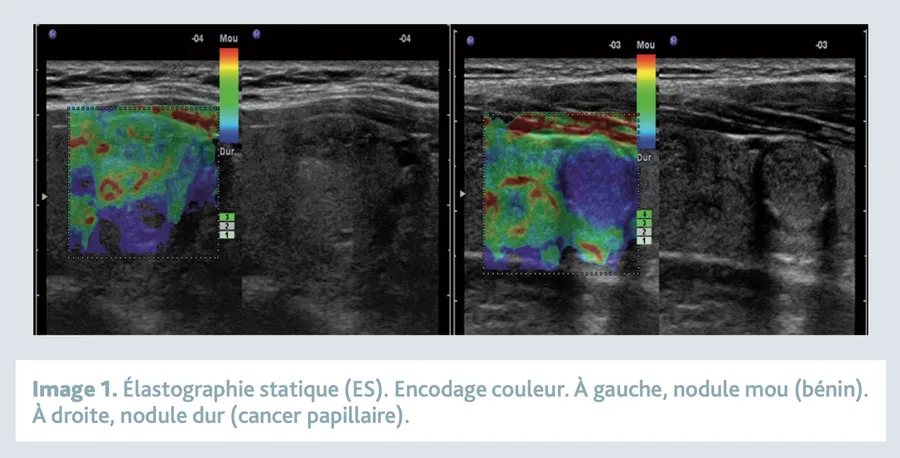

Élastographie thyroïdienne

L’élastographie thyroïdienne est une nouvelle technique prometteuse dans l’évaluation d’un nodule thyroïdien. Elle permet tout simplement une palpation virtuelle du nodule qui ne l’est pas cliniquement.

Cette technique a été développée pour obtenir des informations sur la rigidité d’un tissu de façon non invasive. Étant donné que la thyroïde est un organe assez superficiel, il est possible grâce à cette technique d’obtenir des informations quand à la dureté du tissu et notamment d’un nodule suspect.

La plupart des tumeurs malignes sont caractérisées par la présence d’un parenchyme anormalement rigide qui est la conséquence d’une proportion anormale de collagène et de myofibroblastes dans le tissu.

Certaines tumeurs bénignes peuvent malgré tout présenter une rigidité importante comme les histiocytofibromes. Cette technique permet donc d’orienter le diagnostic.